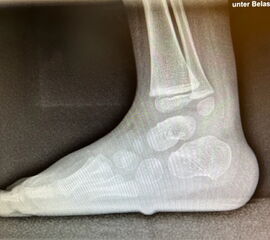

In der Korrektur des schmerzhaften, aber flexiblen Knick-Senk-Fußes oder Plattfußes ist die Schraubenarthrorise mit einem Sinus tarsi oder besser bezeichnet als Canalis tarsi Spacer und alternativ mit einer Calcaneus-Stopp-Schraube seit vielen Jahren ein etabliertes Verfahren und führt zu einer kompletten Korrektur von flexiblen Knick- und Plattfuß-Fehlstellungen (Abb. 7). Die nötige Schnittlänge über dem Sinus tarsi beträgt für beide Verfahren 1 cm.

Abb. 7 a-e: Knick-Senk-Fuß prä- und postoperative Situation (a-b), ventrale und dorsale Ansicht (c-d). Laterale Ansicht des Hautschnittes über dem Sinus tarsi (e).